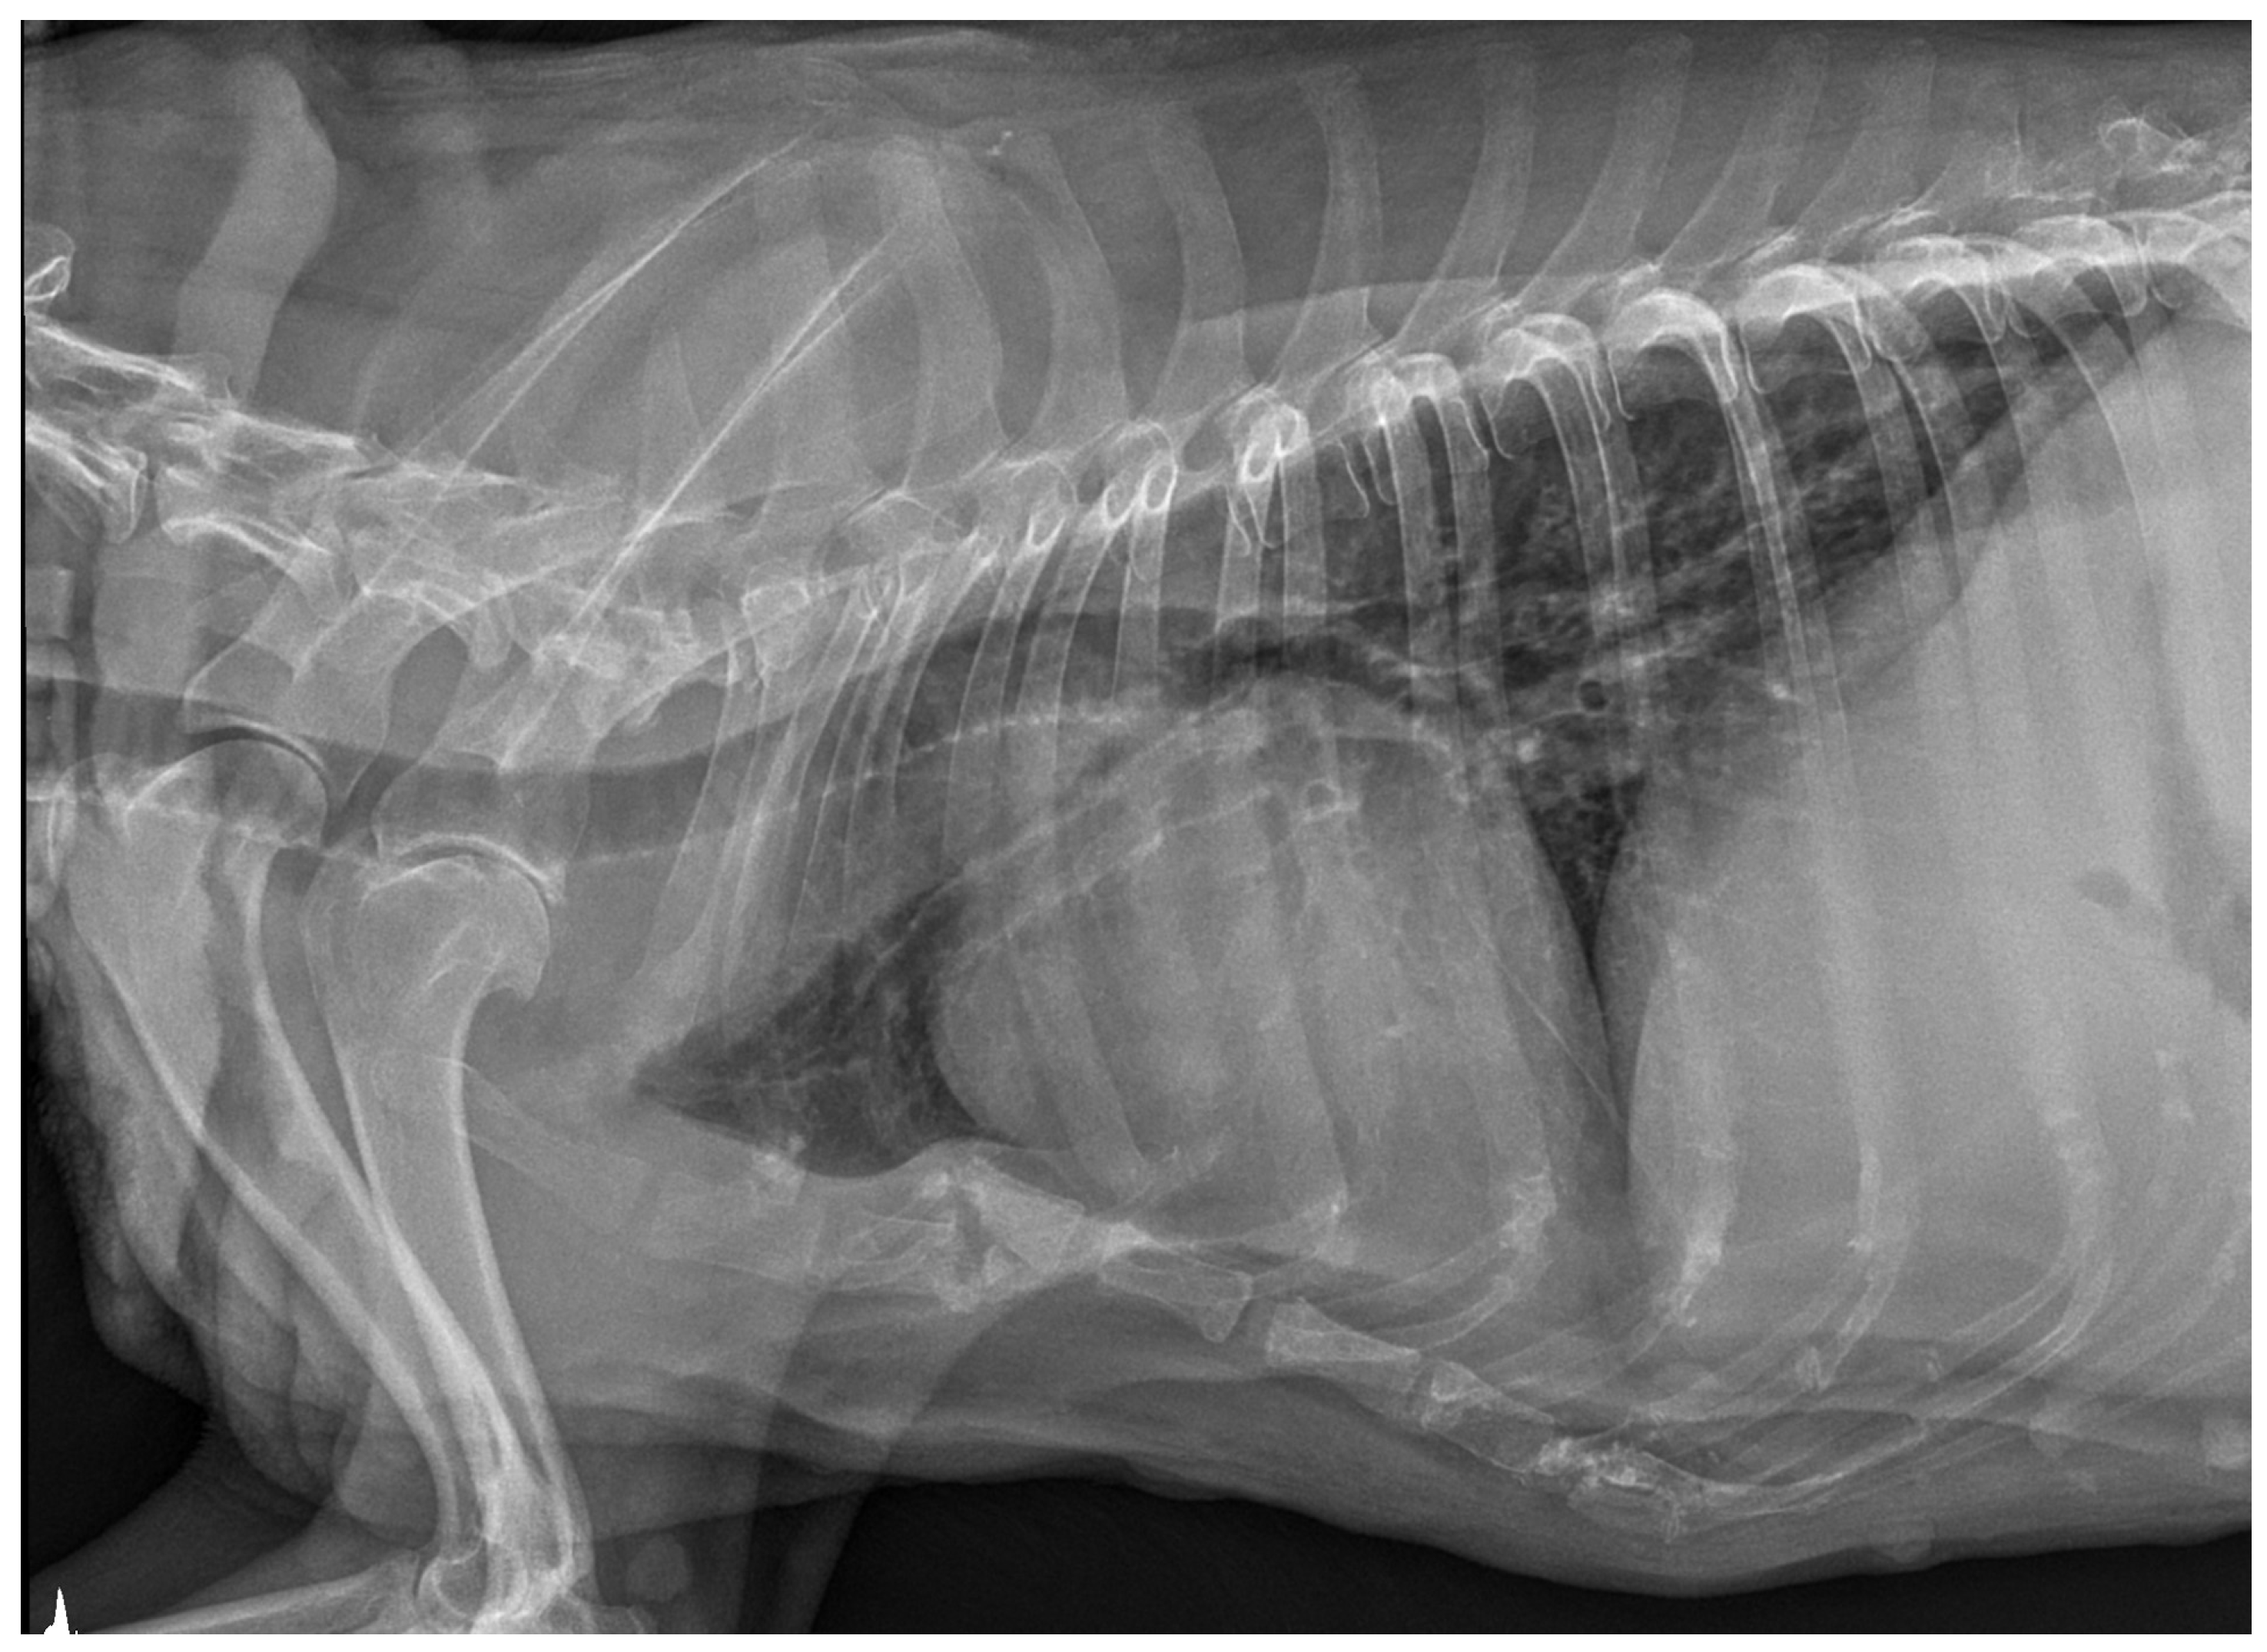

No pathological changes were detected in the lung parenchyma image in the X-ray (Figure 1 and Figure 2). The ultrasound examination revealed in all views a normal, aerated lung pattern. The pleural line was intact, and A-line artifacts were present (Figure 3). The sliding sign was also observed. Echocardiography revealed a mild thickening of the mitral valve leaflets and a slight regurgitation (Figure 4) of this valve. The size of the heart chambers was within the normal range, and myocardial contractility was normal.

Figure 1.

The thoracic X-ray image in the lateral right–left (RL) position shows no pathological alterations within the lung parenchyma and cardiac silhouette. Slight elevation of the trachea in the precordial area is visible.